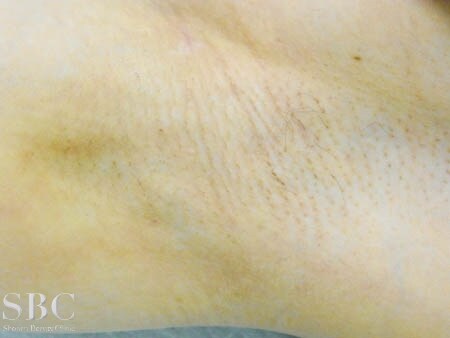

No.105062【わきが・多汗症】日本人初!ベイザー最高位のドクターの資格と称号を取得! あの有名な根こそぎ竹田先生の劇的ビフォーアフター!〜他院の再手術!ワキのニオイは根こそぐもの!右ワキ術後3ヶ月目・傷〜

施術後